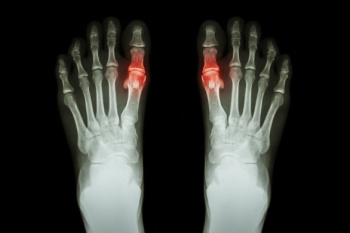

Tophi are firm, swollen deposits that form under the skin when uric acid crystals collect around joints, most commonly in the feet, ankles, or toes. These growths develop over time in people with long-standing gout, a condition in which uric acid builds up in the blood and forms sharp crystals in the joints. The most common locations for tophi are the big toe joint, the heel, and the Achilles tendon. Factors that contribute to tophi buildup include persistent high uric acid levels, delayed treatment, and repeated gout attacks. In the early stages of gout, tophi are not usually present. However, if gout progresses over many years without proper care, these deposits may develop and begin to interfere with joint movement, causing pain and stiffness. In some cases, surgery may be needed to remove large tophi that restrict mobility or damage surrounding tissue. If you have symptoms of tophi buildup associated with gout, it is suggested that you schedule an appointment with a podiatrist for an exam and appropriate treatment options.

Gout is a form of arthritis that is characterized by sudden, severe attacks of pain, redness, and tenderness in the joints. The condition usually affects the joint at the base of the big toe. A gout attack can occur at any random time, such as the middle of the night while you are asleep.